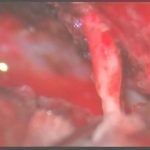

術中写真

摘出 中